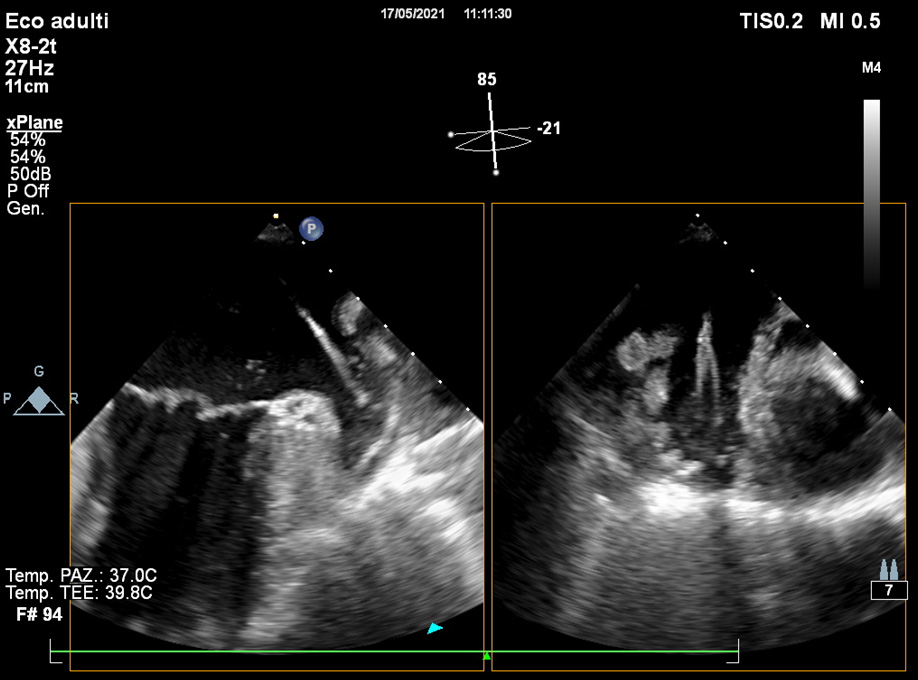

Although 2D TOE represents the routinely modality for pre-operative assessment, the use of 3D TOE gives practical additive information in identifying uncommon morphologies [12], and its use is increasing. While its anatomic estimations are superior to 2D TOE, slow temporal resolution of 3D TOE and lacking professional guidelines still represent limitations of this technique.

Detailed characterization of the LAA body and orifice shapes can facilitate device selection (Fig. 5).

Fig. 5.The use of 3D TOE provides useful additive evaluation about unusual morphology or irregular orifices.